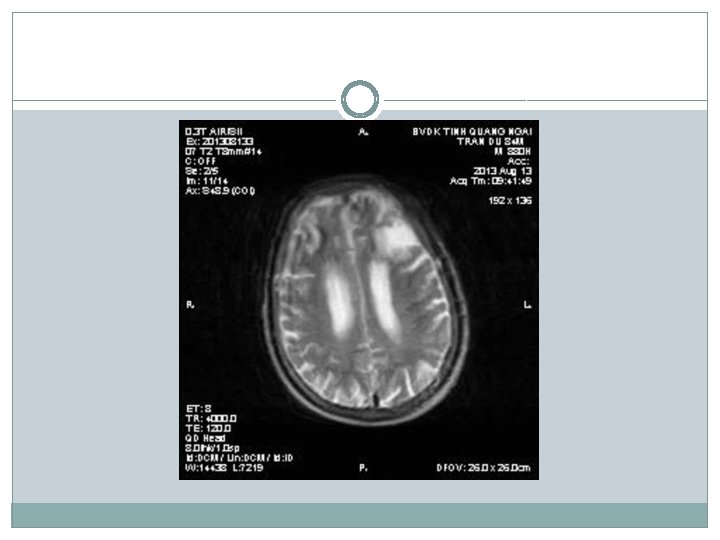

�Siêu âm có nang thận phải # 34 mm �X-quang tim phổi bình thường; thoái hóa cột sống thắt lưng �Điện não: chủ yếu sóng chậm Theta, ưu thế vùng trán (T) �Điện tim bình thường �CT scan não: Nhồi máu não thùy trán (T) �MRI não: Nhồi máu thùy trán (T), teo vỏ não thùy trán + não thất giãn nhẹ

Chẩn đoán �Tuy nhiên có điểm chưa phù hợp trong chẩn đoán bệnh Parkinson: khởi bệnh run cả hai bên đối xứng; hình ảnh học MRI cho thấy có teo vỏ não, có biểu hiện rối loạn tâm thần sớm